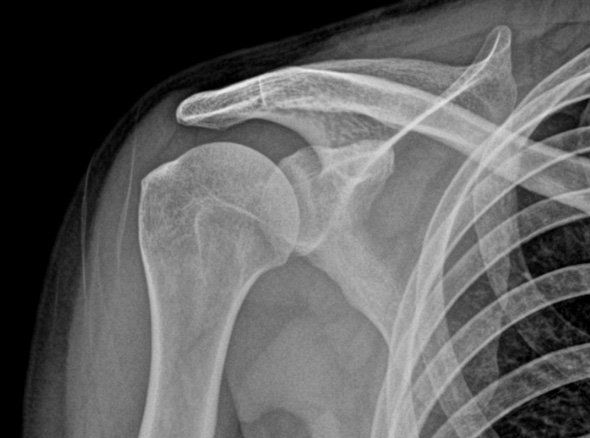

오십견은 어깨를 감싸고 있는 관절 조직인 관절낭에 염증이 발생하면서

유착되어 어깨의 움직임이 제한되고 통증이 유발되는 질환입니다.

오십견은 얼어버린 어깨라고들 부릅니다. 어깨가 움직이는 범위가 점점 줄어들면서

통증을 느끼는 질환입니다. 의학적인 용어로는 동결견, 유착성 관절낭염이라고도 합니다.